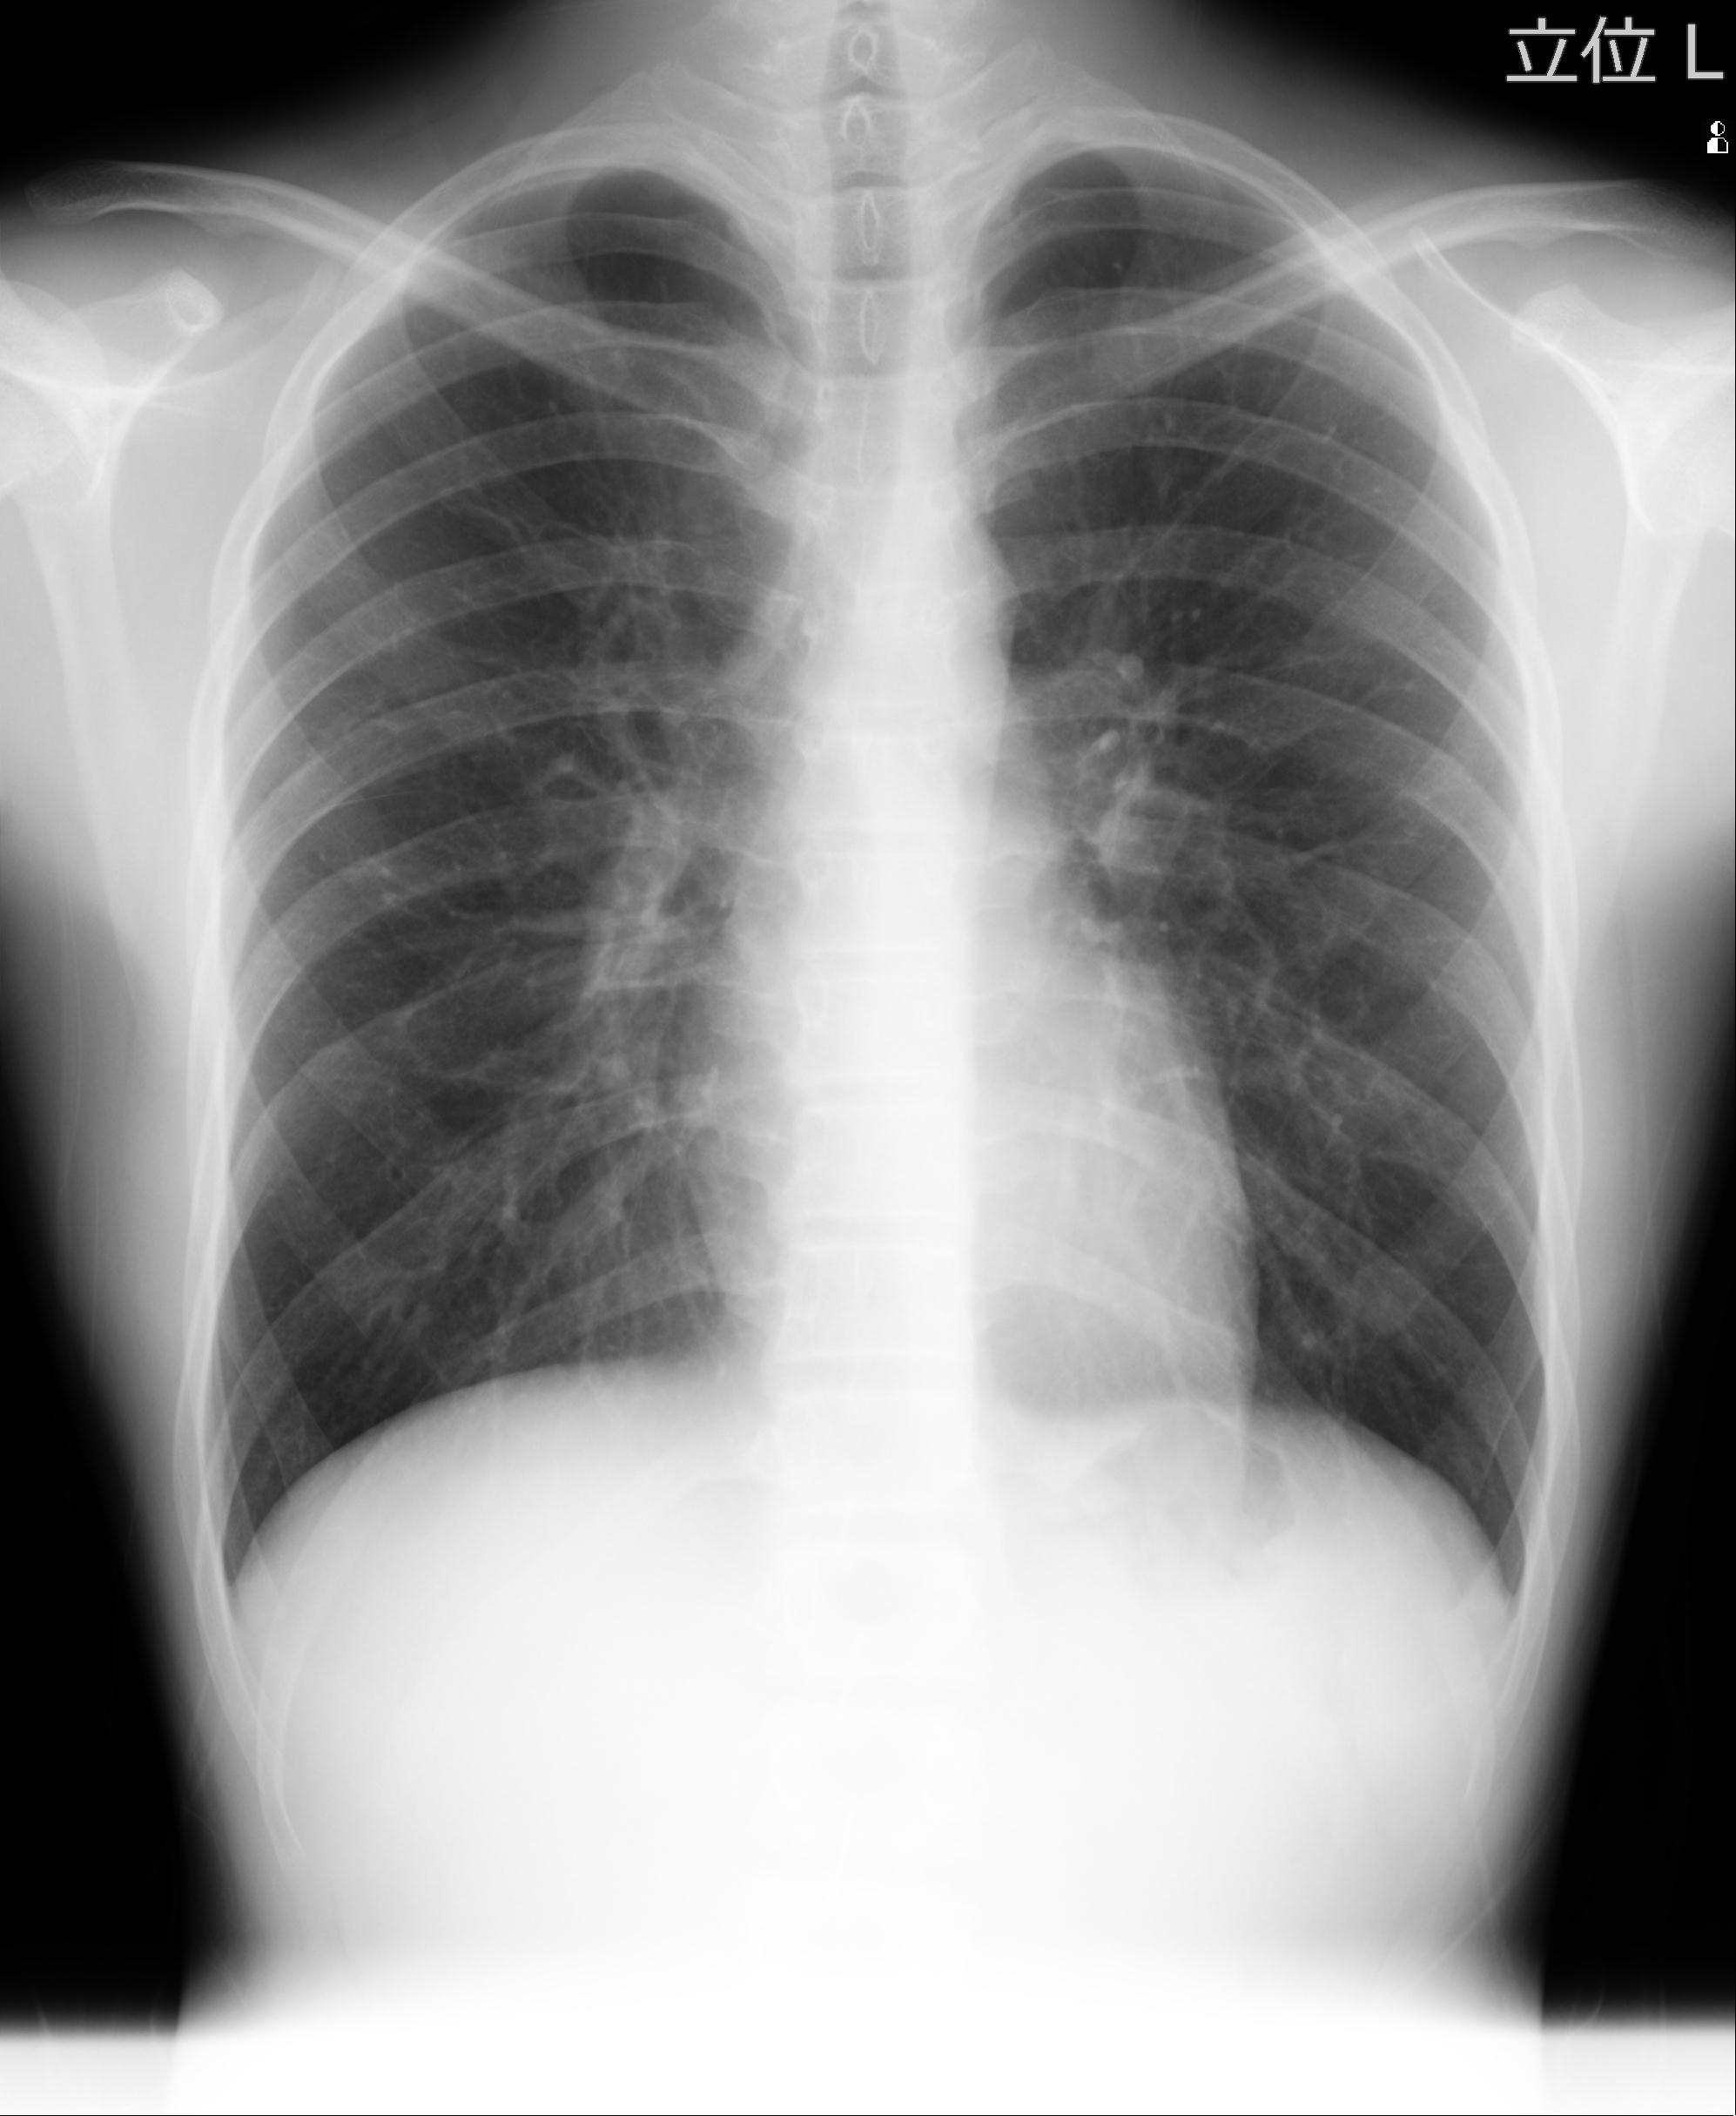

60058 3/9 11/4 右肩 2R+MRI 73歳男性 肩腱板損傷